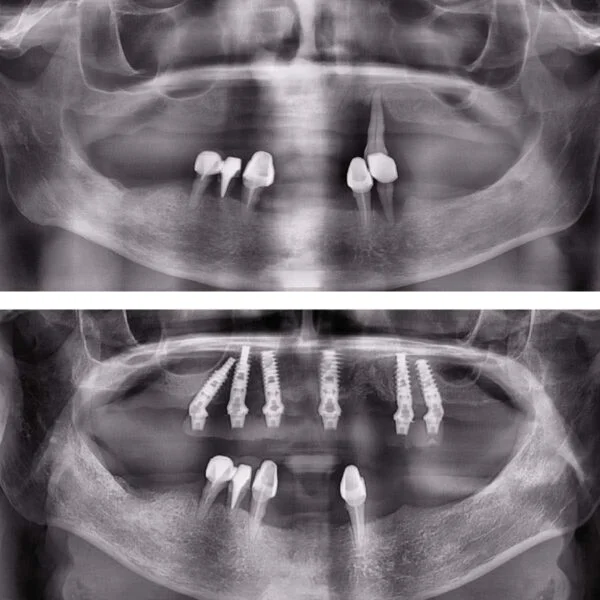

Implantul dentar este adesea recomandat deoarece prezintă foarte multe avantaje, iar, de multe ori, este unica soluție pentru protezarea unei edentații.